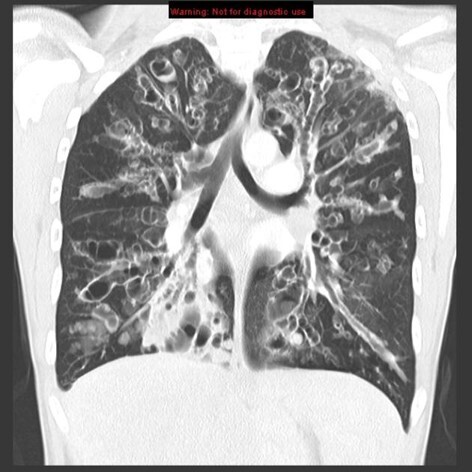

1

Not at all

2

3

4